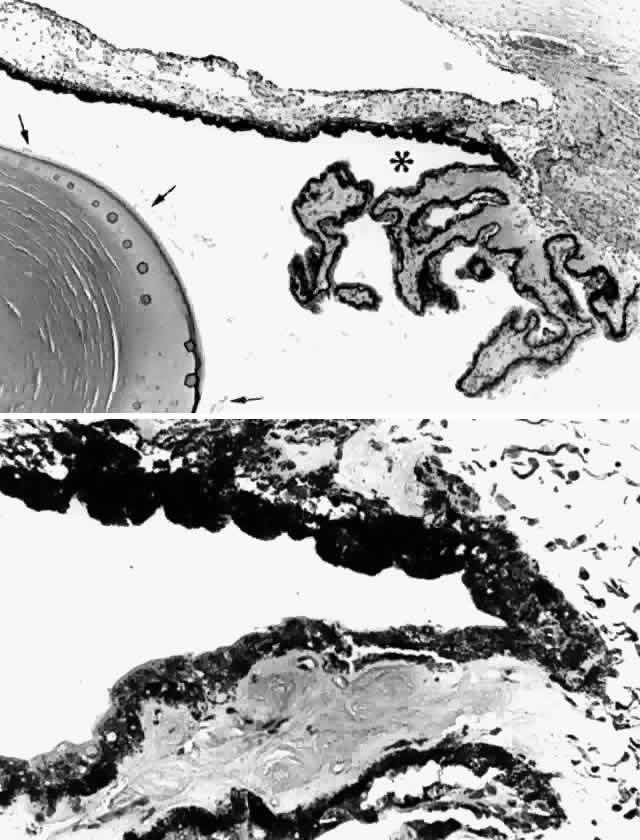

A surface anatomic region of considerable interest anteriorly is the ciliary sulcus, which is the valley created posterior to the iris at its origin from the ciliary body. This sulcus is bounded posteriorly by the ciliary processes and more centrally by the anterior zonular fibers and lens surface (Fig. 7A), making it a natural site for supporting the haptics of a posterior chamber intraocular lens (IOL). Although the ideal site for a posterior chamber IOL is within the lens capsular bag, such placement is not possible when the lens capsule is absent or where the capsule-zonular diaphragm lacks sufficient strength, such as in pseudoexfoliation when some of the zonules have ruptured. To choose an appropriate size of IOL for support and centration in this space, it is important to consider the diameter of the sulcus. In 41 postmortem eyes this diameter correlated significantly with axial length determined echographically, with a mean sulcus diameter of 11.2 mm (SD = 0.3 mm).8 A bimodal distribution of ciliary sulcus diameters was noted with a clustering of smaller diameters in shorter eyes. It has been suggested that it results from incomplete posterior migration of the pars plicata from the peripheral iris during embryonic growth. In another postmortem study,9 the mean sulcus diameter was 11 ± 0.37 mm, slightly smaller than the mean corneal diameters (11.32 ± 0.29 mm) in the same eyes. The authors found, in addition, that the mean distance from the corneal limbus to the ciliary sulcus measured externally was 0.9 mm, which would be of interest for transscleral suture fixation of haptics.

Fig. 7. The ciliary sulcus. A. Cross section through a ciliary sulcus (asterisk) of a 61-year-old patient. Arrows indicate zonular fibers. Lens is on left. B. Irregular iris pigment (above) and ciliary nonpigment epithelial cells line the sulcus. (hematoxylin-eosin, A, X 43; B, X 165)

The irregular contour of the sulcus area has been well described, particularly narrowing of the sulcus caused by occasional bands and folds extending from the ciliary processes onto the back of the iris.10 These extensions probably derive from the incomplete migration of ciliary processes off the peripheral iris, as previously mentioned,8 and could misdirect haptics into the easily penetrated iris or ciliary body during IOL insertion (Fig. 7B). This information has led to recommendations for smaller total IOL diameters in posteriorly fixated lenses,11 which should help avoid haptic puncture or erosion into the uvea and possible vascular occlusions.8,12